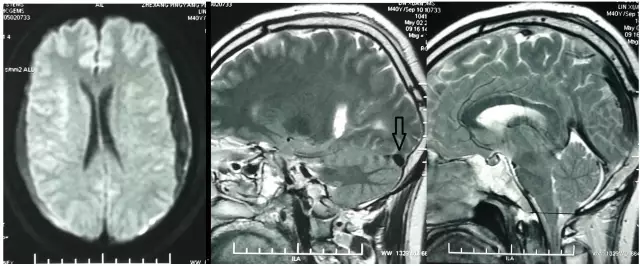

但术后2天再次出现头痛,不能缓解,5月2日复查头颅MRI提示硬膜下血肿术后复发,伴小脑下坠,脑沟及小脑上方仍可见较多脑脊液,四脑室变小,颅内静脉系统扩张明显(箭头所示见横窦扩张)(图3)。

图3. 术后1周(5月2日)复查头颅MRI显示左侧硬膜下血肿术后复发,伴小脑下坠,脑沟及小脑上方仍可见较多脑脊液,四脑室变小,颅内静脉系统扩张明显(箭头所示见横窦扩张)。